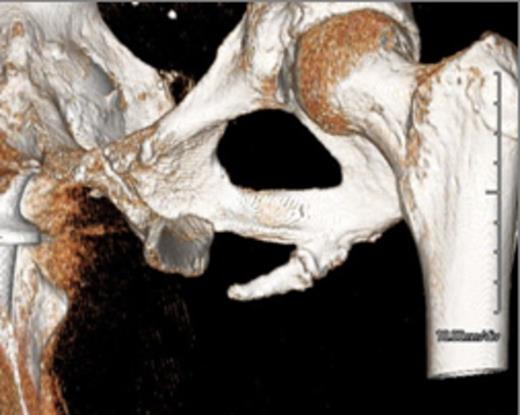

Representative images, including: a plain radiograph (Figure 1), 3D reconstructed computed tomography (Figue 2) and T1 coronal magnetic resonance imaging (Figure 3) indicated a bony excrescence from the inferior aspect of the left ischium measuring 1.7 x 1.1 cm. MR without gadolinium did not show any surrounding inflammatory changes. No aggressive features were seen on the studies. Review of a previous CT scan from 2 years prior to the most recent study, demonstrated a stable lesion.

3D Reconstructed Computed Tomography demonstrating the pelvic digit

The above studies were suggestive of a pelvic digit. The patient’s chief complaint was painful intercourse and she elected to proceed with a resection. A pelvic digit was further confirmed after resection (Figure 4). Pathology found no evidence of malignancy and the patient was discharged without pain and able to ambulate without support of a walker. The removed pelvic digit had two bony segments that formed a pseudoarticulartion or joint, visible in images A and B. Follow up via a telephone communication indicated that her dyspareunia had resolved.

Pelvic digits remain an anomaly. Literature reports have suggested various origins of the pelvic digit, including congenital formation, myositis ossificans, or traumatic avulsion.(1-3,5,6) In this case, the defining features were that it was well corticated with a pseudoarticulation between bony segments, resembling a digit. This is most consistent with a congenital etiology. Typically this would occur prior to the sixth week of fetal life in the mesynchymal stage.(6,8)